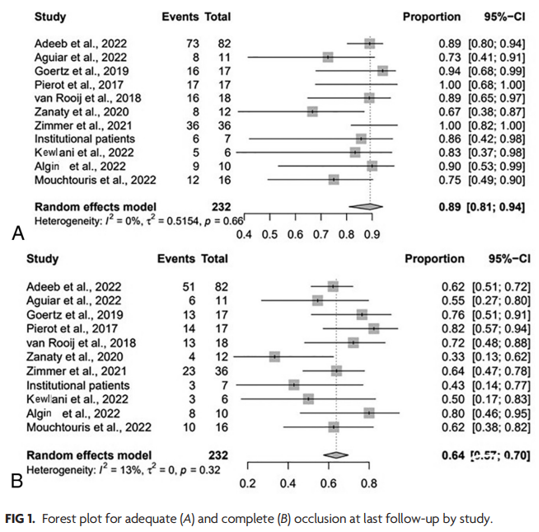

对从WEB研究开始到2022年5月间Scopus、EMbASE、MEDLINE、Web of Science和Cochrane对照试验注册中心使用WEB装置治疗侧壁动脉瘤患者的所有研究进行了系统综述。共纳入10项研究,包括285例患者,288个侧壁动脉瘤。

最后一次随访的充分闭塞率(adequate occlusion rate)为89%(95% CI,81%-94%;I2,=0%,P=.66)。动脉瘤宽度(aneurysm width)(OR=0.5;P=.03)是完全闭塞的唯一显著预测因子。

复合安全性结局(composite safety outcome)为8%(95% CI,3%-17%;I2=34%),术中并发症发生率为6%(图2B);血栓栓塞并发症为2%,出血性并发症为1%,装置放置问题1%,血管夹层发生率1%。术后并发症发生率为1%,全因死亡率为2%(95% CI,1%-7%;I2=0%)。